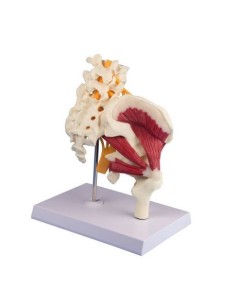

Modèle de maladie de l'articulation de la hanche 3B Scientific 1019506